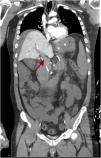

We report the case of a 37-year-old male, with no significant past medical history, who, five days after receiving the Janssen Covid-19 vaccine, began experiencing language impairment, disorientation, and psychomotor restlessness. A brain CT scan revealed the presence of left middle cerebral artery ischemia (Fig. 1), as well as a platelet count of 25 000/mm3, which raised suspicion of vaccine-induced thrombotic thrombocytopenia (VITT). This suspicion was later confirmed with positive antibodies against platelet factor 4. Despite treatment with fondaparinux, corticosteroids, and immunoglobulins, the patient's disease progression was poor, with development of abdominal distension with peritonitis and rapid respiratory deterioration that eventually requiring mechanical ventilation. The abdominal CT scan performed at six hours revealed the presence of enterocolic, pancreatic, and gastric ischemia with extensive thrombosis of the portomesenteric axis (Fig. 2 and Fig. 3). Ultimately, the patient passed away